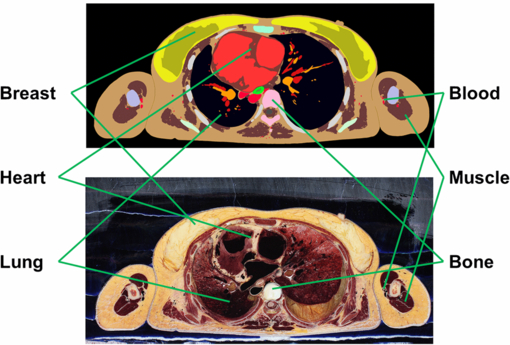

The segmentation work was carefully performed in collaboration with professional anatomists. First, the slice images were taken at 2 mm intervals, and 825 images out of the total 5901 were selected for phantom construction. These images were then imported to Photoshop®CS4 (Adobe Systems, Inc., San Jose, CA) software for segmentation. Most of the organs were segmented manually with a screen digitizer (CINTIQ 15X, WACOM Co., Ltd, Japan); organs distributed throughout the body and clearly distinguishable, such as certain muscles and the blood, were segmented automatically using Photoshop®CS4's Color Range function. The skeletal system was also segmented automatically by CT imaging. Artifact-induced erratic structure segmentations were manually corrected. Figure 2 shows the example of a segmented image and a corresponding original color image.

Figure 2. Example of segmented image with corresponding original color image.